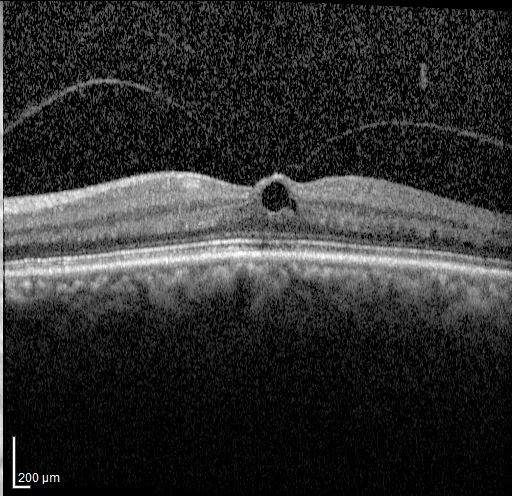

How macular holes form and how surgery can restore central vision.

Read article